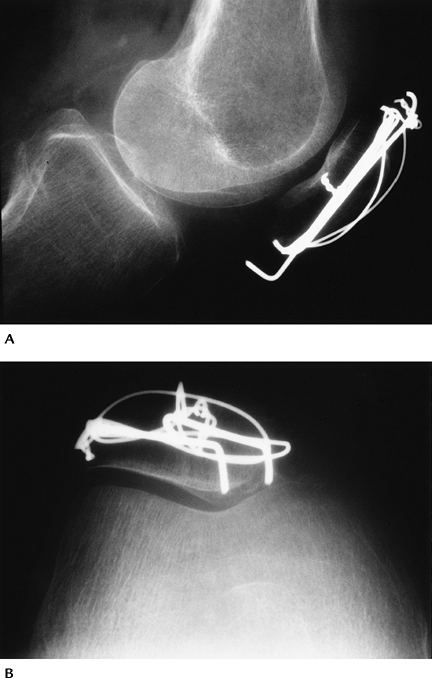

Skeletal Trauma: Patellar Fractures

Key Facts

Patellar fractures account for 1% of all skeletal fractures.

The mechanism of injury is direct trauma

(motor vehicle accidents 28%, falls 68%) or indirect trauma (4%), such

as quadriceps contraction. -

Types of patellar fracture: transverse or oblique 34%; comminuted 16%; longitudinal 28%; apical or basal 28%.

A bipartite patella involves the upper outer quadrant. It usually is bilateral and should not be confused with a fracture.

Routine radiographs (AP, lateral, patellar views) usually are diagnostic.

Treatment includes reduction with

internal fixation for displaced fractures. Fractures with less than 2

to 3 mm of displacement and articular surface congruency can be treated

conservatively (casting). Badly comminuted fractures may require

partial or complete patellectomy. -

Complications

Osteoarthritis

Nonunion

![]() |

FIGURE 5-2 AP (A) and lateral (B) radiographs of a bipartite patella (arrow).

FIGURE 5-3 AP (A) and lateral (B) radiographs of a comminuted displaced patellar fracture.

FIGURE 5-4 Lateral (A) and patellar (B) views after reduction with K-wires and tension band. The articular surface is reduced.